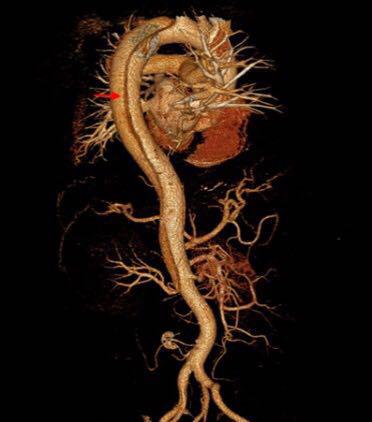

主动脉夹层发病时就像一个被吹大的气球。当血液从裂口进入主动脉壁,把管壁中间的那层膜撕开、分裂、扩展,大量血液涌进去,又形成一个新的血管腔。当循环血液渗入主动脉夹层之内,只能流入不能正常流出,就会像吹气球一样,越“吹”越大,最终导致主动脉破裂,病人会在瞬间死亡。大多数的患者在病发前会感觉胸痛异常,烦躁不安、大汗淋漓、有濒死感,甚至因疼痛而昏厥。不过也有一部分患者病发时毫无预兆,一发病两三分钟内猝死,无法实施抢救。

5、数字减影血管造影(DSA)是诊断主动脉夹层的有效手段,但价格昂贵。